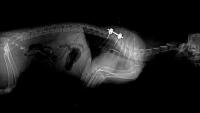

Thailand makes history with nation's first cat pacemaker surgery

This groundbreaking achievement was made possible by veterinarians from Chulalongkorn University’s Faculty of Veterinary Science.